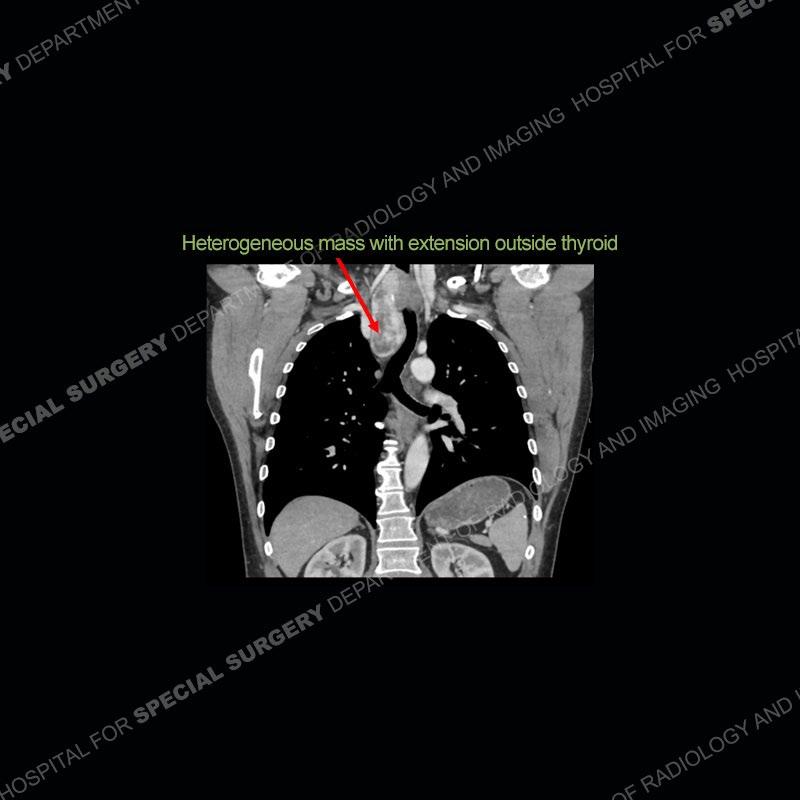

Findings

The chest radiographs demonstrate a leftward deviation of the trachea. CT images demonstrate a large, somewhat heterogeneous mass of the thyroid that extends outside the confines of the thyroid tissue. There is a subtle, enhancing soft tissue mass of the proximal right humerus. Slightly prominent mediastinal lymph nodes are present with additionally, multiple supraclavicular lymph nodes.

Over the years we have shown a couple of these cases which may be considered more so an “eye test” then anything else. In clinical practice, these are often very difficult cases as the initial finding of the tracheal deviation may be easily overlooked. Screening radiographs are clearly most often used to assess cardiopulmonary function before induction of anesthesia but at times other findings of great and unfortunately grave consequence can be found. The evaluation of the incidental thyroid mass on CT and MRI is an ever changing situation. Parameters such as age of patient, extension outside of the thyroid, enhancing nodules, and local invasion of lymph nodes are evaluated to see if a lesion needs to be further evaluated.

Although not strictly a part of the evaluation of an “incidental” thyroid lesion, evaluation of the adjacent lymph nodes and bony structures can also be quite important. In this case, there is an enhancing mass of the right humerus. This is very subtle and can only really be recognized by evaluating the density of the bone. Typicaly marrow will have a fatty density or nearly fluid density. As the density, as in this case, approaches soft tissue an infiltrative process must be entertained. Thyroid mets are markedly vascular accounting for the areas of enhancement of the humeral mass. The mediastinal and supraclavicular lymph nodes although not individually enlarged, should raise suspicion of an underlying inflammatory/neoplastic process.